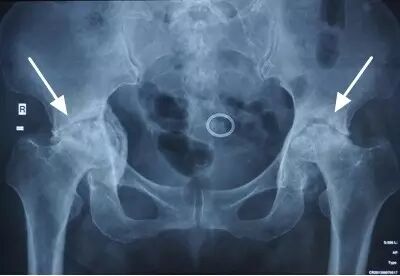

II期和III期的患者治疗方法相同,因为此时股骨头虽然还没有变形,暂时还不需要行人工关节置换术,但是股骨头已经出现空洞,随时股骨头就会塌陷变形,所以单纯的股骨头减压术是不能达到治疗效果的。这时就需要在股骨头减压的同时,植入一根支撑棒,顶住股骨头空洞区,防止股骨头在负重的情况下过早塌陷。其他治疗同之前相同,口服以上药物,定期复查,密切观察病情发展,尽量避免重体力劳动和爬山爬楼。

以上为股骨头坏死减压加支撑棒植入术示意图和术后X线片